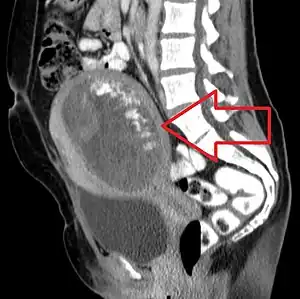

![]() | |

| Molar pregnancy seen on CT scan, sagittal view | |